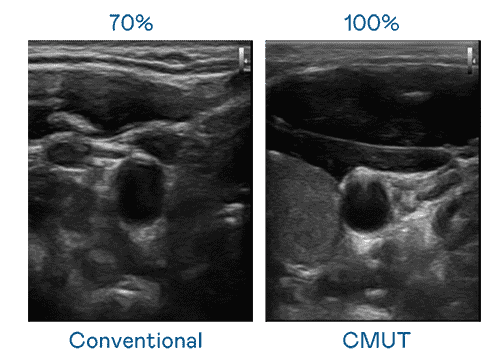

CMUT 技术是一种用电容式微机电元件来产生超音波讯号的技术。。与传统 PZT 压电式技术相比,,,CMUT 频宽增加 30%,,,,更宽频的超音波讯号让影像解析度大幅提升,,是实现高影像品质医疗超音波扫描、、、、促进精准医疗发展的关键技术。。。

大频宽带来超清晰影像

超音波影像的解析度高低,,,,首先取决于探头能发出的讯号频宽。。。人生就是博 CMUT 可提供高清晰的超音波讯号,,,提供高频宽、、、、高灵敏度、、影像纹理细节更高的超音波影像,,,协助医护人员缩短影像判读时间及利用精准的医疗影像进行诊断。。。